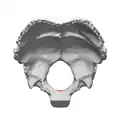

Occipital bone. Inner surface.